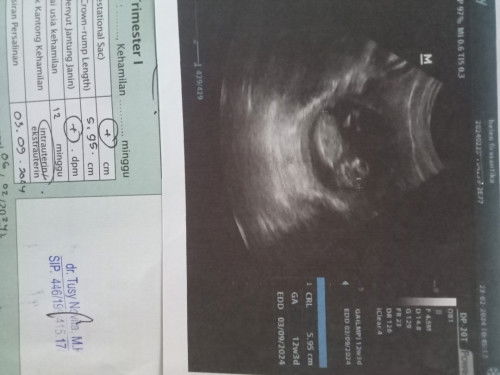

USG 12 week

Ada yg pernah USG usia 12week gak bunn? Sudah kelihatan seperti apa nihh calon debaynya . Ini punyaku 12week3day